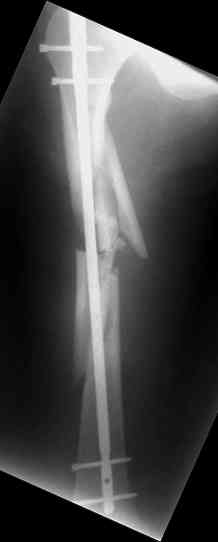

Re: С3-перелом бедра как лечить дальше?....

Dmitry Katritsa 25 Сентябрь 2007, 20:56

одна проблема в моей компьютерной неграмотности(не смог прикрепить снимки), а другая в том, что связь с пациентом потеряна и,насколько я понял в своем регионе ему посоветоваться не с кем, кроме главного врача который отреагировал на выбранную нами тактику так: "там тебя использовали в качестве подопытного кролика...".

Надеюсь сейчас показать перелом, а потом синтез.